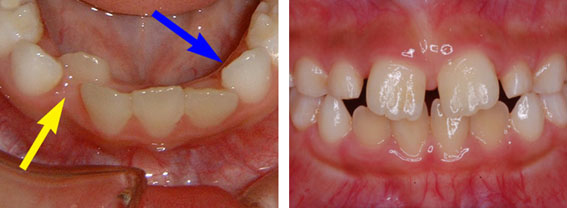

下の写真、どう思われますか?どちらのお子さんも歯科健診では「むし歯0本」と診断されます。

Aの写真のお子さんは全ての歯をがんばって治療しました。同じむし歯0本でもこんなに違います。今の歯科医療では機能の回復はできますが、治療しても元の健康な状態(歯)へ戻すことはできません。お口の中の環境(むし歯ができる環境)を変えなければいくら治療してもまたすぐにむし歯を作ってしまいます。 「カリエスフリー」という言葉をご存知ですか?もちろん、「むし歯の治療が終わりました」という意味ではありません。カリエスフリーというのは、むし歯の経験がまったくない状態をいいます。@の写真のお子さんのように現在も過去もむし歯が1本もなく、治療をした経験がない状態です。むし歯を作って治療するよりも作らないことを目指すようにしましょう。 日本人の20歳でのカリエスフリーはたったの4%しかいません。お子さんをカリエスフリーにするためには専門の歯科医院で歯みがきの仕方、フッ素の利用法、むし歯ができにくい食生活の指導を受けることが早道です。 やはり病気は治療するより、予防するものです。一生いい歯と付き合うためには必要なことです。